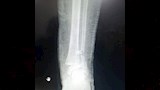

وتضمنت الإصابات كسرًا مضاعفًا في مركز النمو أسفل عظمة القصبة اليسرى، وكسرًا أسفل عظمة الشظية اليسرى، وخلعًا كاملًا في مفصل الكاحل الأيسر، وفقًا لخطورة الإصابات وتأثر مركز النمو، سارع الفريق الطبي إلى اتخاذ قرار بالتدخل العاجل منعًا لتأثير مستقبلي على حركة الطالب أو نمو العظام.

ونجح الفريق في رد الخلع بشكل فوري، أعقبه إجراء عملية تثبيت جراحي للعظام باستخدام أسلاك معدنية، وسط متابعة دقيقة لضمان إعادة العظام إلى موضعها الطبيعي وتفادي أي مضاعفات محتملة، إذ أسهمت سرعة التدخل ودقته في استقرار حالة الطالب سريعًا، قبل أن يغادر المستشفى في حالة جيدة بعد تلقيه الرعاية الطبية الكاملة.